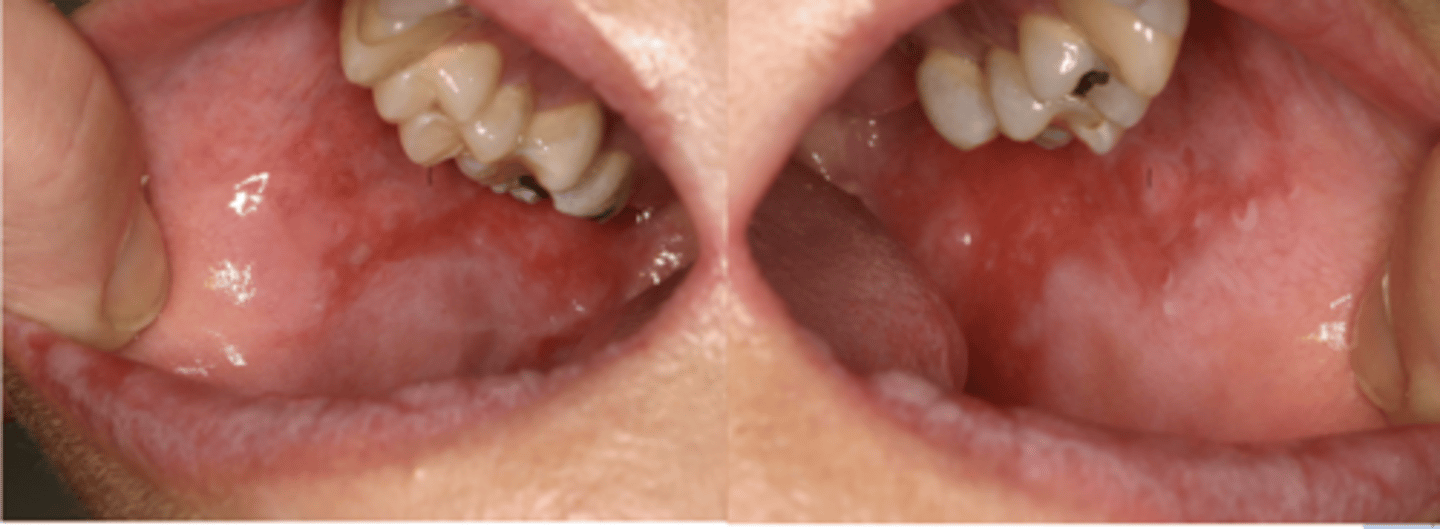

Mucous Membrane Pemphigoid

These are clinical features of what condition?

- Often restricted to gingiva

- 25% with oral lesions develop eye lesions

- Positive Nikolsky sign

Patient presents with these lesions along with ocular lesions including symblepherons, entropions, trichiasis. What is the most likley differential?

Patient presents with an autoimmune disorder with autoantibodies to hemidesmosomes. What condition do you suspect?

Patient presents with these lesions along with ocular lesions and an autoimmune disorder with autoantibodies to hemidesmosomes. What condition do you suspect?